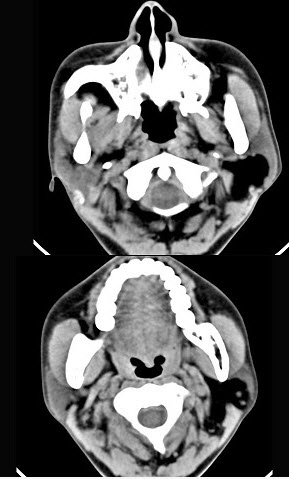

女性50岁,左侧面部肿胀,CT检查如图,应考虑为()。

A、左侧腮腺囊腺瘤

B、左侧腮腺囊肿

C、左侧腮腺脂肪瘤

D、左侧腮腺错构瘤

E、左侧腮腺炎

正确答案:

C